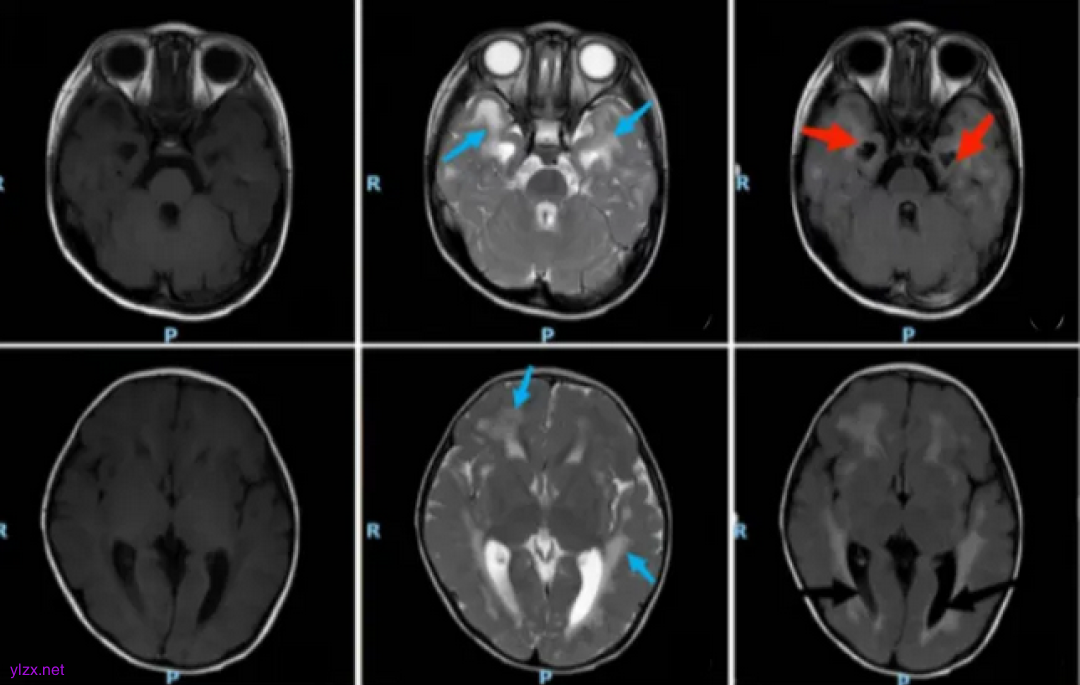

患者头颅MRI

AGS综合征神经系统表现为:颅内多发钙化灶、脑白质病变、脑脊液慢性淋巴细胞增多。